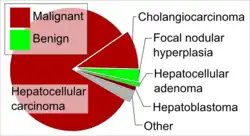

Hepatocellular adenoma (also known as hepatic adenoma or hepadenoma) is a rare, benign liver tumor. It most commonly occurs in people with elevated systemic levels of estrogen, classically in women taking estrogen-containing oral contraceptive medication.[1]

Hepatic adenoma is usually detected by imaging, typically an ultrasound or CT, as a hyperenhancing liver nodule. Given that several liver tumors appear similarly on these imaging modalities, a multi-phase contrast-enhanced imaging study such as CT or MRI may be used to provide more information.[3][4] The significance of making a specific diagnosis is that, unlike other benign liver tumors such as hemangioma and focal nodular hyperplasia, hepatic adenomas have a small but meaningful risk of progressing into a malignancy.[3] Although imaging provides supportive information, a definitive diagnosis of hepatic adenoma requires biopsy of the tissue.